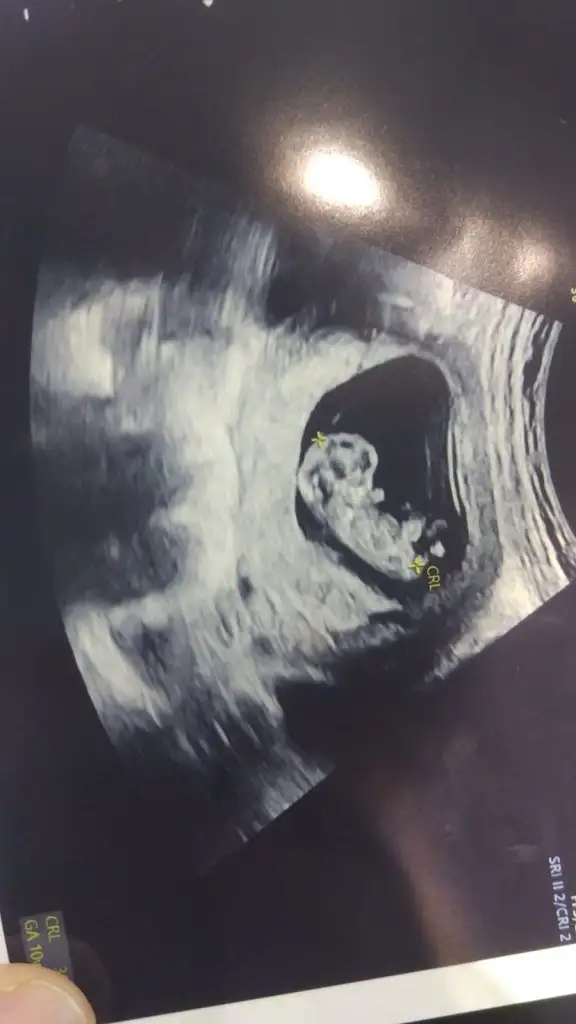

Bu da benim minnak11+3 . 4,85 cm olmuş. Yalnız fotolar biraz korkunç görünüyor